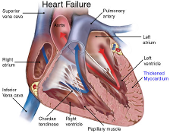

₦42,000.00Treat Heart Failure - caused by weakening of the heart so that it can not pump sufficient blood for normal circulation.

₦28,000.00Treat Heart Palpitation - A treatment for the heart when it is beating rapidly in an abnormal manner